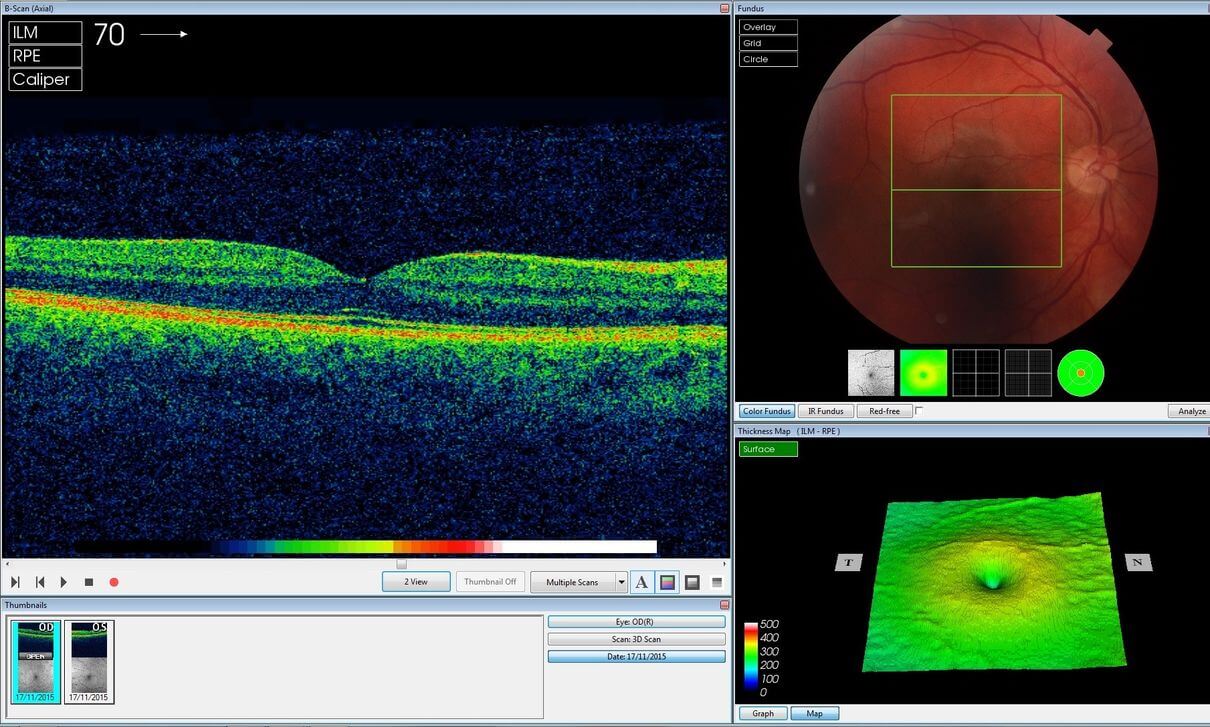

О новом исследовании рассказывает журнал Engadget и они пишут, что искусственный интеллект для выявления болезней использует метод оптической когерентной томографии (сокращенно ОКТ). ОКТ основана на неинвазивной бесконтактной визуализации структур глаза. При этом ОКТ-снимки чем-то напоминают УЗИ-изображения, но с гораздо более высоким разрешением. Такая высокая четкость позволяет определять различные структуры и аномалии развития, являясь чем-то вроде «биопсии без удаления ткани».

Именно проблему долгой расшифровки решает ИИ. В основе новой системы лежит 2 нейросети: одна переводит необработанные снимки OКT в карту трехмерных тканей, после чего ставит предварительный диагноз. Вторая же анализирует полученную трехмерную карту и проверяет точность диагноза первой, попутно определяя, насколько срочно пациенту требуется медицинская помощь. По словам ведущего инженера Google DeepMind Алана Картикексайнама,

«Наша карта не только позволяет создать 3D-модель глаза, но и выявляет заболевание, указывая, в какой именно части зрительного органа расположен его очаг. Нейросети обучены на 877 сканах OCT и 14000 трехмерных изображениях тканей глаза, проверенных квалифицированными специалистами.»